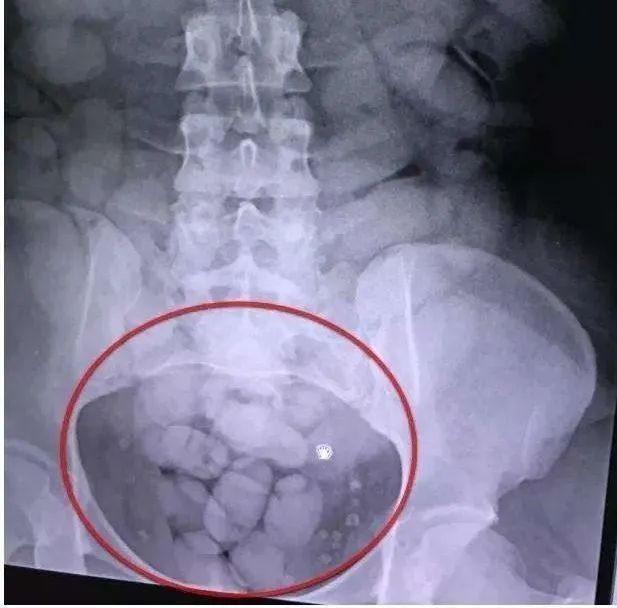

当腹部的拍片结果出来的时候,一切真相大白,X线显示病人的胃里面和肠道里面有上百个大拇指大小的块状物体。

(为隐私保护,本图片来源于网络)

原来,这个18岁的小伙子是个毒贩,为了通过安检,用体内藏毒的方式从云南运毒到上海。但是由于包装不严,藏毒的包装物破损,大量的毒品迅速吸收导致了毒品中毒,差点送命。警方随即在医院包了一个单间病房,进行24小时监控。

胃里面的小块毒品,用胃镜取异物的方式取出来一部分,肠道内的毒品,采用促进排便的办法排泄。但是等了三天,由于毒品本身会减慢肠道活动,所以一包毒品也没拉出来,反而肠子被彻底堵住了啥都出不来,变成了肠梗阻,最后只能外科手术开刀把所有毒品都取出来。